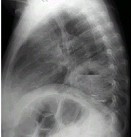

- 单项选择题女,36岁, 发热,胸痛咳脓痰十余天, 胸部正侧位如图,最可能的诊断为 ( )

A、左下肺周围型肺癌并空洞形成

B、左下肺脓肿

C、左下肺空洞型肺结核

D、左侧包裹性液气胸

E、急性胃扩张